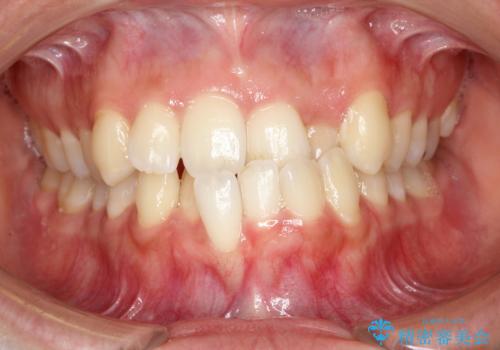

- 主訴:「右上犬歯を引っ込めて、歯並びをキレイにしたい」

右上の八重歯を気にされてご来院されました。結婚式を控えていたため挙式にまでに可能な限りキレイにしたいとのことでした。